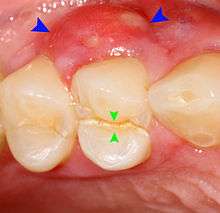

Decay (green) with apical abscess (blue)